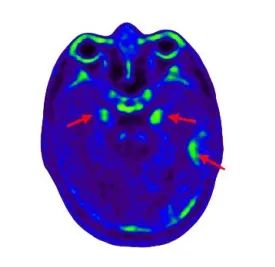

▲患者头颅 Tau PET-CT 阳性,tau蛋白沉积局限于颞叶,提示处于疾病早期